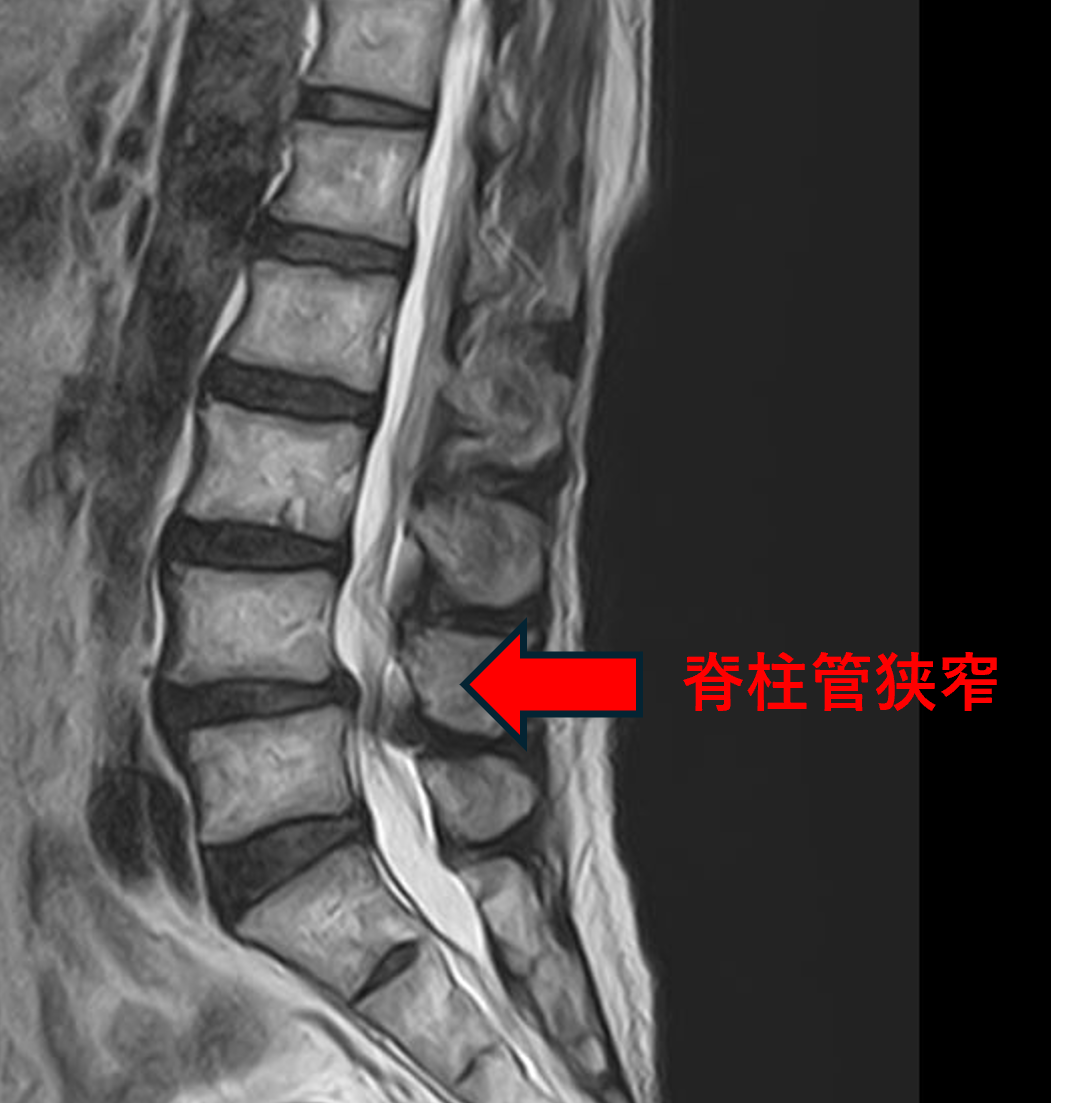

- L3/4、5/s – 椎間板変性、膨隆

- L4/5 – 椎間板変性、膨隆、椎間孔狭窄、脊柱管狭窄、変性すべり

以上のことが画像上認められました。

L3/4、4/5、5/sの椎間板所見による脊柱管の圧排が、症状の原因の可能性が高い。